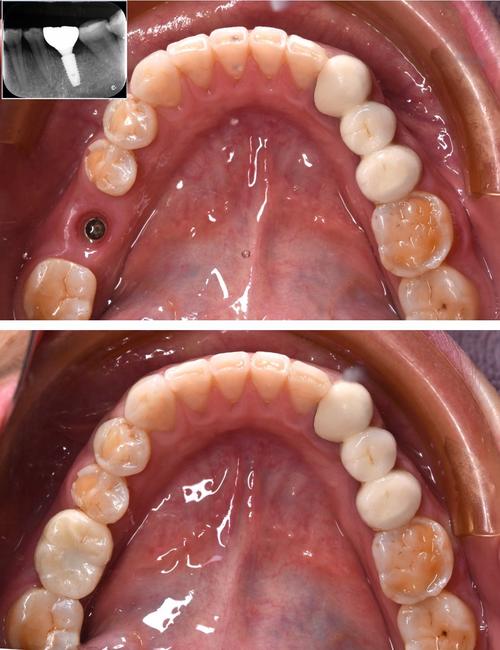

| 种植手术 | 局部麻醉下,在牙槽骨植入种植体(类似“人工牙根”),微创手术无需缝合,术后即可戴临时牙冠。 | 1-2 |

| 牙冠修复 | 骨结合后,取模制作永久牙冠(全瓷冠、烤瓷冠等),佩戴并调整咬合,完成最终修复。 | 7-14 |